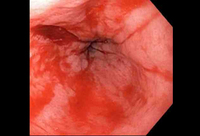

Mallory-Weiss tear after adrenaline injection (the bleeding has stopped, allowing better visualisation of the lesion)

From the collection of Juan Carlos Munoz, MD, University of Florida